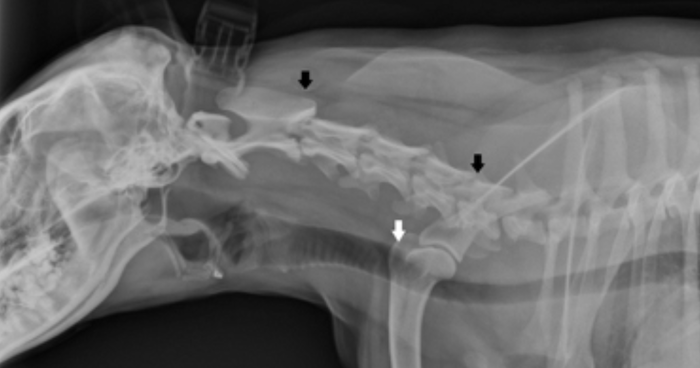

Radiographs

These were taken to assess the patient’s forelimbs to see if the cause of pain could be identified. A narrowed cervical disk space was noted between C2-C3 and C5-C6 (black arrow) which could be the source of pain in her neck. There was also mild mineralization near the shoulder joint (white arrow).